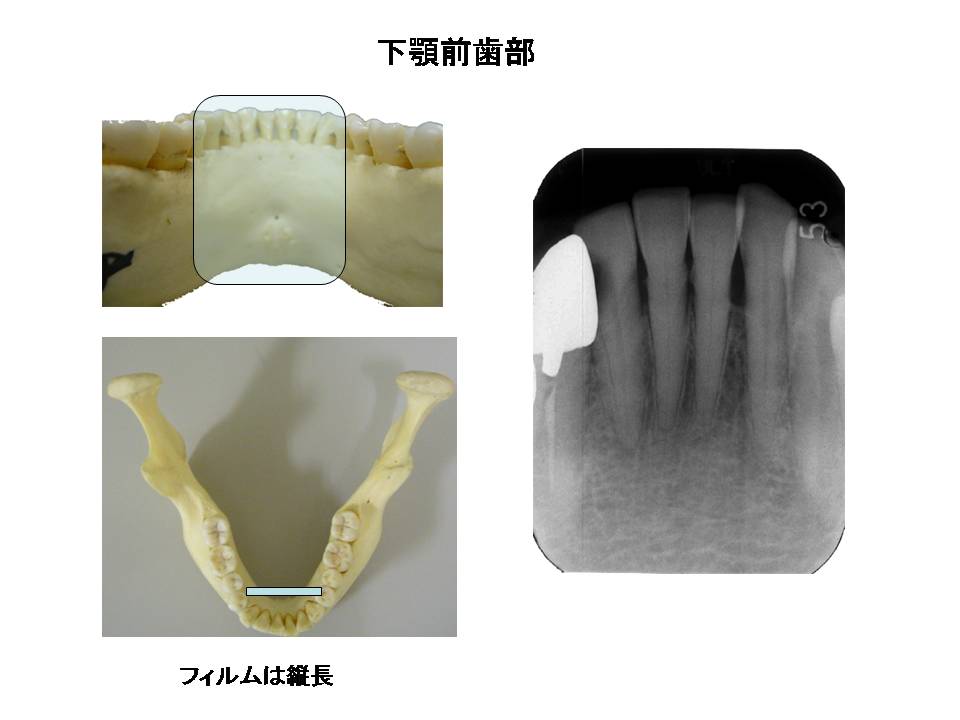

口内法(二等分法・咬合法)撮影の解剖